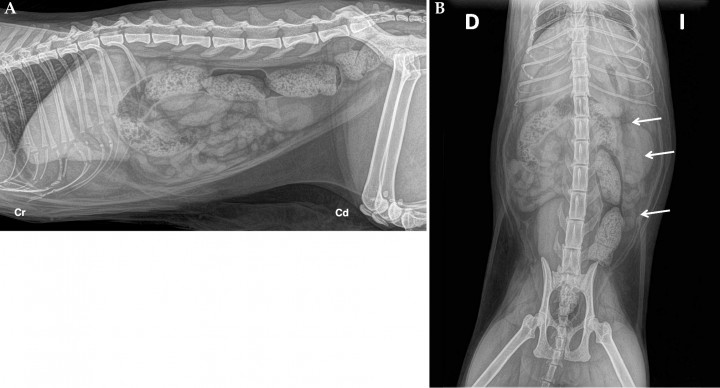

Para valorar el tamaño hepático, se realizó un estudio radiológico abdominal. Se obtuvieron proyecciones lateral derecha y ventrodorsal del abdomen (Fig. 1). En la proyección ventrodorsal, en el abdomen medio-izquierdo y caudomedial al bazo, se observó una estructura tubular y tortuosa de opacidad tejido blando que se superponía con la silueta renal y que se continuaba caudalmente lateral al colon descendente. El hígado presentaba un tamaño normal. El resto de estructuras abdominales no presentaban alteraciones radiológicas evidentes. Dicha estructura presentaba una localización y recorrido atípicos para tratarse de un asa intestinal. Por este motivo, el primer diagnóstico diferencial que se valoró, teniendo en cuenta la historia clínica y la analítica sanguínea, fue una estructura vascular anómala.

<p>(<strong>A</strong>) Proyección lateral derecha del abdomen. (<strong>B</strong>) Proyección ventrodorsal del abdomen. En la proyección VD se observa una estructura tubular y tortuosa de opacidad tejido blando caudomedial al bazo y superpuesta con la silueta renal izquierda que se dirige caudalmente por el lado izquierdo y cranealmente medial al bazo (flechas). Esta estructura no se observa en la proyección lateral. Cr: craneal, Cd: caudal, D: derecha. I: izquierda.</p>

Figura 1

(A) Proyección lateral derecha del abdomen. (B) Proyección ventrodorsal del abdomen. En la proyección VD se observa una estructura tubular y tortuosa de opacidad tejido blando caudomedial al bazo y superpuesta con la silueta renal izquierda que se dirige caudalmente por el lado izquierdo y cranealmente medial al bazo (flechas). Esta estructura no se observa en la proyección lateral. Cr: craneal, Cd: caudal, D: derecha. I: izquierda.

La apariencia de las comunicaciones esplenosistémicas en gatos ha sido descrita recientemente. El hallazgo radiográfico característico es la presencia de una estructura de opacidad tejido blando, tubular y tortuosa, en el abdomen izquierdo caudal al bazo y lateral al riñón izquierdo en la proyección ventrodorsal. Este signo radiográfico se conoce como signo del espagueti.[ Specchi S, Panopoulos I, Adrian AM, Spattini G, Morabito S, Paek M. A “spaghetti sign” in feline abdominal radiographs predicts spleno-systemic collateral circulation. Vet Radiol & Ultrasound. 2018; 59(1): 13-17. [PubMed] ] En el presente caso se observó dicho signo, por lo que el estudio radiológico abdominal representó una primera herramienta en la aproximación al diagnóstico de la comunicación esplenosistémica.